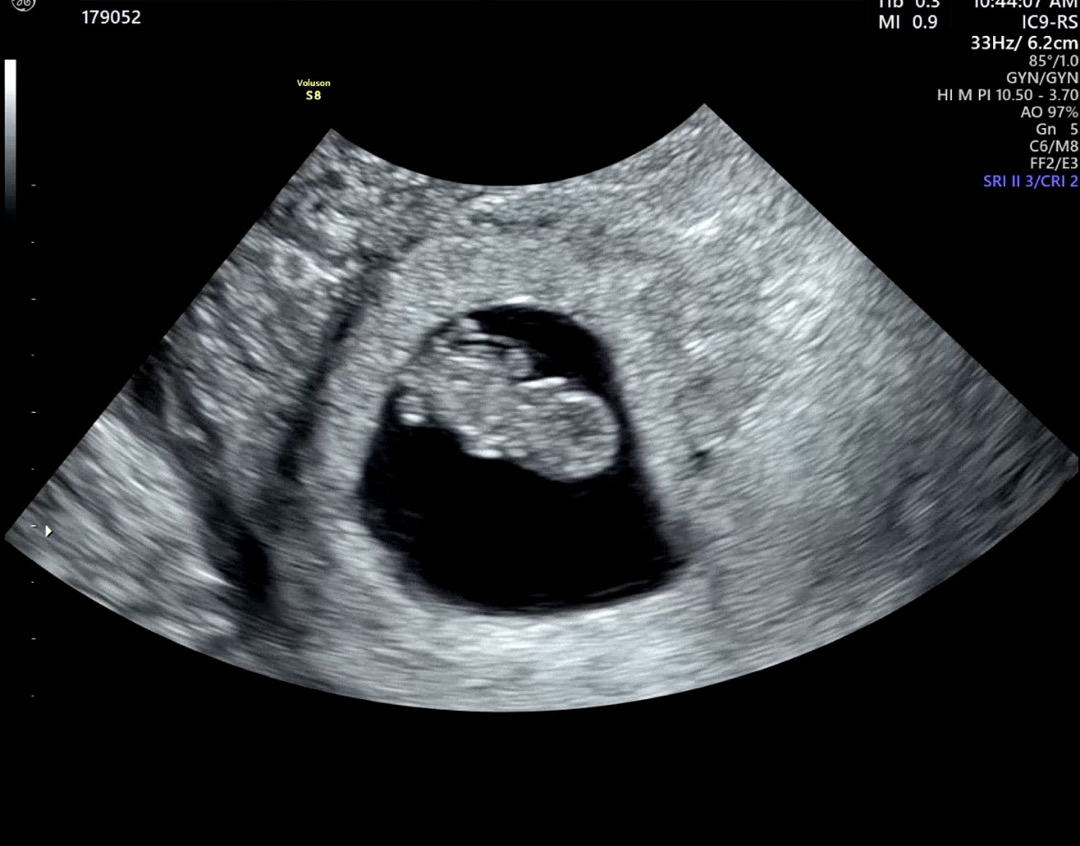

8주차 젤리곰 자랑합니다

어쩜 이렇게 젤리곰 그대로 나왔는지 너무 귀여워요 처음 보고 내 아가 맞나?! 싶을정도로 동글동글 귀여웠던 ㅋㅋㅋ 8주차 되니까 드디어 좀 사람 같네요! 건강히 잘 자라줘서 너무 고마운 마음 뿐~~ 8주차 맘들 분만 까지 화이팅 입니닷 💕